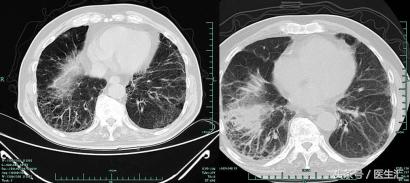

2013-9-25肺CT

2013-10-13 肺部CT:慢支、肺气肿。两肺间质性病变,对照13.9.25老片右肺斑片影增多,感染考虑。右上肺钙化灶。